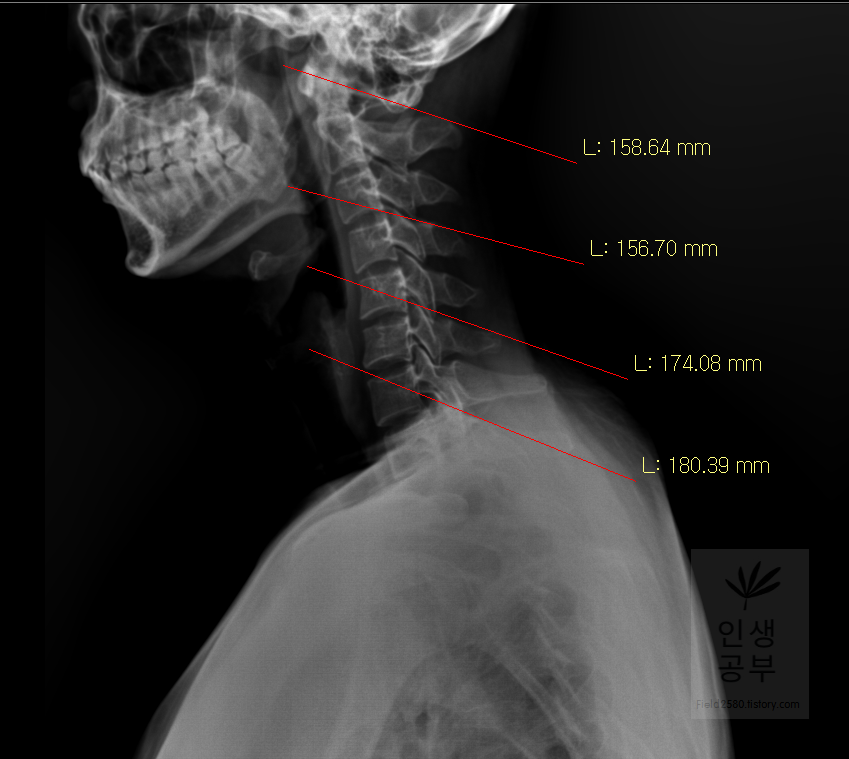

선 긋기를 이용해서 Cobb각을 그린다고 가정했을 때 측정하려고 하는 곳을 처음에 누르고 드래그로 쭉 끌어다주면 위와 같은 선이 생기고 선의 길이가 자동으로 측정됩니다. 첫 번째 목뼈(C1) 선을 그리기 위해 제일 튀어나온 앞쪽 부분 가운데 지점에(Center of Anterior arch) 점을 찍어줍니다. 후궁(Posterior arch) 제일 좁은 부위 가운데 지점에 점을 찍어줍니다. 두 점을 연결해주는 선을 그어줍니다. 이 선 이름을 고리 뼈 선(APL : Atlas Plane Line)이라고 합니다. 점은 조금 더 정확하기 위해서 하는 것이 찍어도 되고, 점을 찍지 않은 상태에서 선을 그으셔도 무방합니다.

일곱번째 목뼈 추체 밑면(Inferior endplate of C7)과 평행한 선을 그어줍니다.